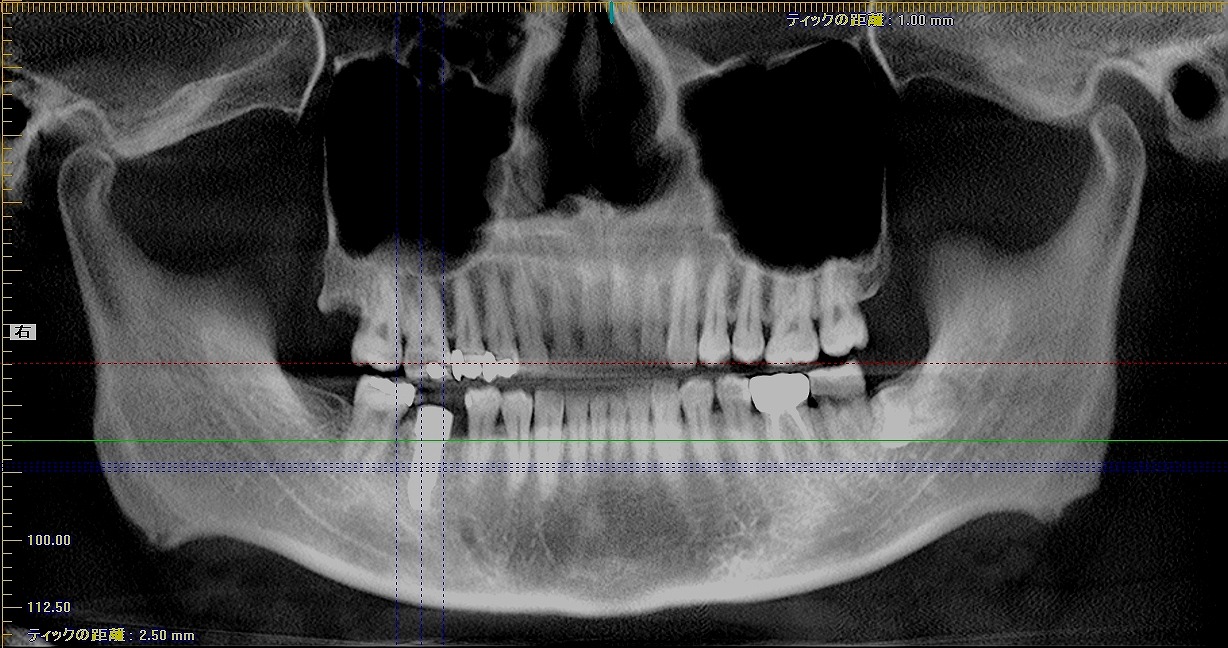

インプラント埋入時になります

5mmの11,5mmというインプラントを埋入しています

術前術後のパノラマになります

綺麗に入りました